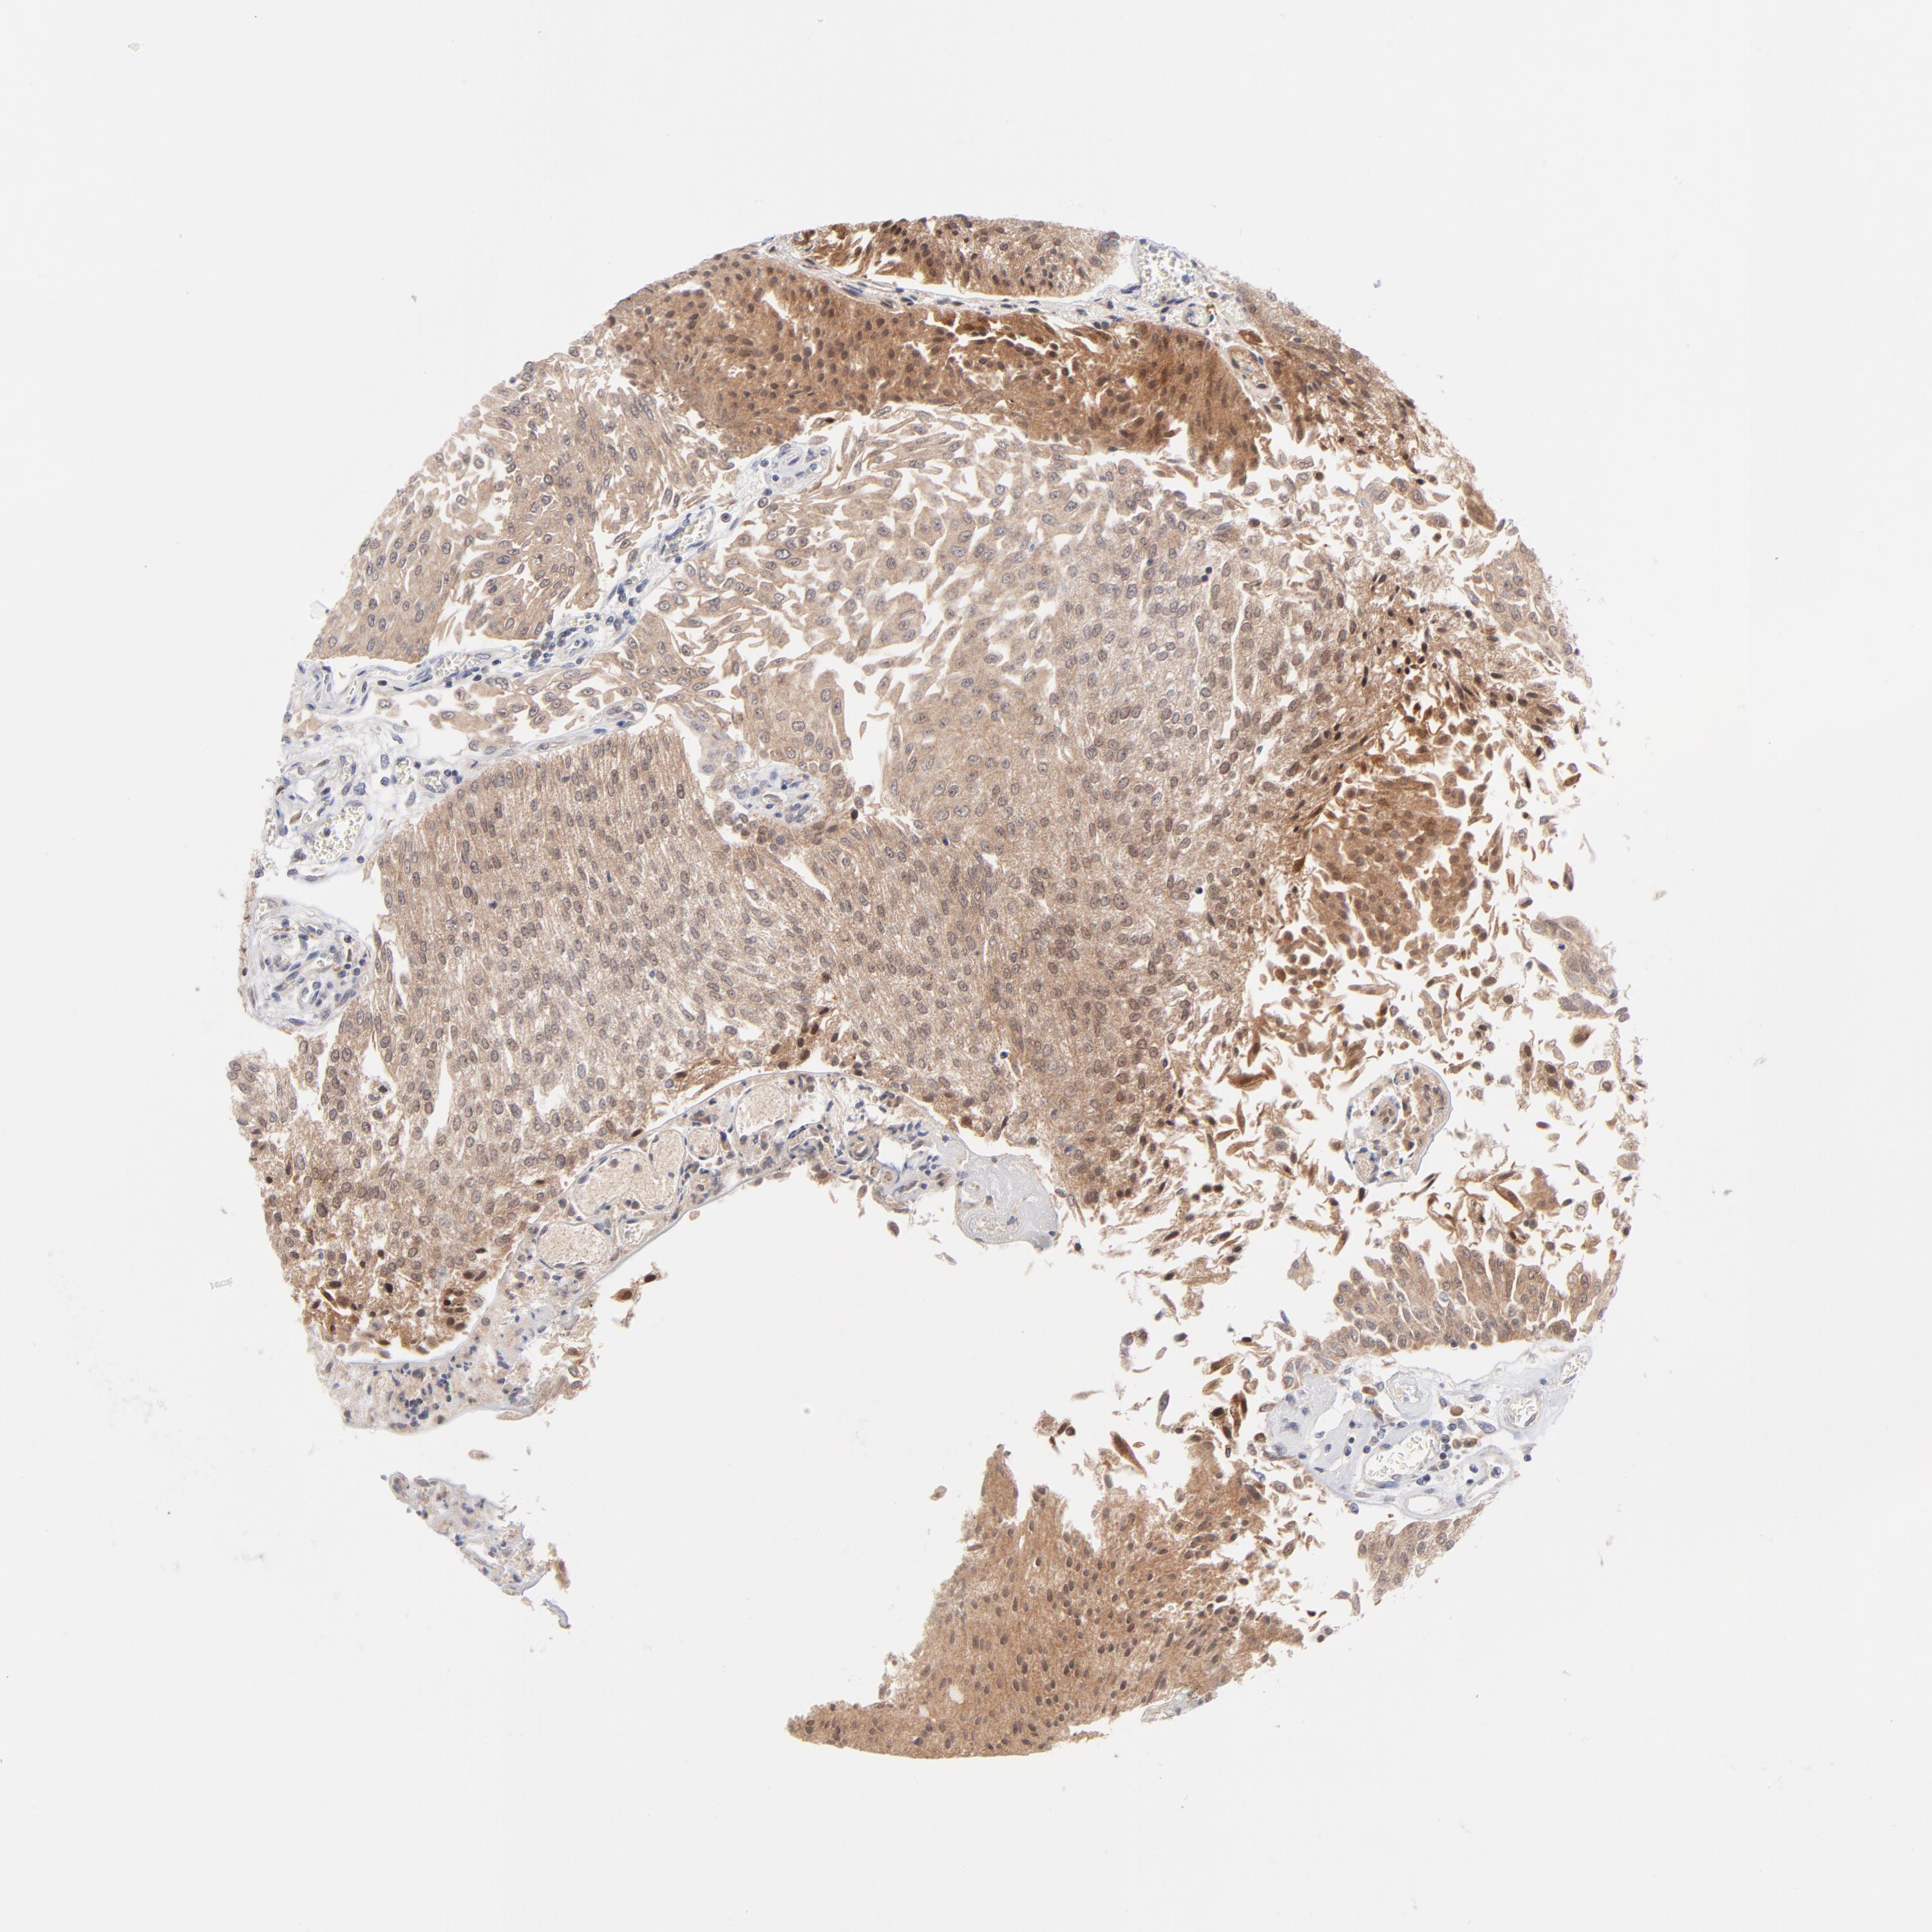

UROTHELIAL CANCER - Protein expressioni

A mouse-over function shows sample information and annotation data. Click on an image to view it in a full screen mode. Samples can be filtered based on level of antibody staining by selecting one or several of the following categories: high, medium, low and not detected. The assay and annotation is described here.

Note that samples used for immunohistochemistry by the Human Protein Atlas do not correspond to samples in the TCGA dataset.

Antibody stainingi

Antibody staining in the annotated cell types in the current human tissue is reported as not detected, low, medium, or high, based on conventional immunohistochemistry profiling in selected tissues. This score is based on the combination of the staining intensity and fraction of stained cells.

Each image is clickable and will lead to virtual microscopy that enables deeper exploration of all samples and also displays staining intensity scores, fraction scores and subcellular localization as well as patient and tissue information for each sample.

Antibody HPA003628

Staining

High

Medium

Low

Not detected

Intensity

Strong

Moderate

Weak

Negative

Quantity

>75%

75%-25%

<25%

None

Location

Nuclear

Cytoplasmic/membranous

Cytoplasmic/membranous,nuclear

Urothelial carcinoma, High grade

Urothelial carcinoma, Low grade